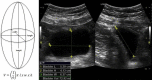

Methods and materials: This was a single institution retrospective study of 20 patients (390 CBCT scans) who received postprostatectomy RT. Each patient received a daily US before treatment. CBCT alignment was performed 3 times a week. The bladder and rectum were contoured on each CBCT and a session dose was recorded. A mixed-effect model was used to estimate trajectory slopes of radiation exposure with organs-at-risk volume increase. Slope differences by V40/65 for prostate fossa (PF) and pelvic lymph nodes (PF/pLN) were tested using a 3-way-interaction term with Bonferroni correction.

Results: For the 20 patients, 10 received treatment to PF and 10 received RT to the PF/pLN. Predefined bladder constraints were V65 < 50%, V40 < 70%, and rectal constraints were V65 < 35%, V40 < 55%. The CBCT bladder volume (76-578 cm3) was greater than the pretreatment bladder US (87-466 cm3) due to volume filling between measurements (r = 0.8 ± 0.05). Mixed model detected a statistically significant 3-way interaction (P < .01) for bladder volume and V40/65. Both PF and PF/pLN patients showed improvement in V40/65 with an increase in bladder volume. For PF patients, bladder constraints were met when the US volume was >108 cm3 and for PF/pLN patients when the US bladder volume was >200 cm3. Rectal filling showed no association with CBCT volume.